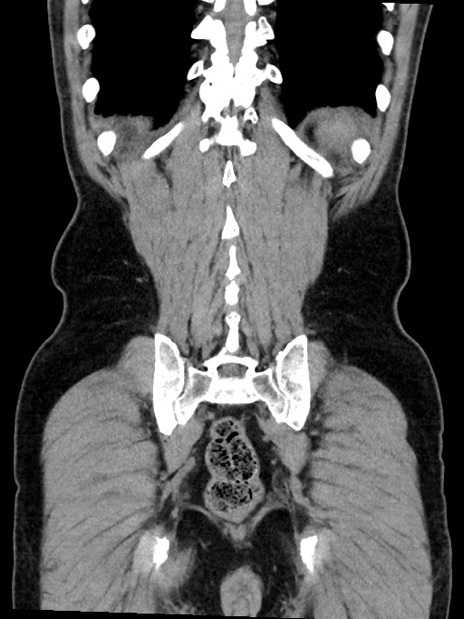

症例35(冠状断像)

症例

【症例】70歳代 男性

【主訴】腹部膨満、嘔吐

【現病歴】昨日より腹部膨満感出現。本日増悪し、仙痛出現。嘔吐あり、受診。

【既往歴】糖尿病、胆摘後

【身体所見】BP 149/80mmHg、HR 74/min、BT 35.9℃、腹部:膨満、軟、圧痛なし。腸雑音減弱あり。上腹部正中切開瘢痕あり。

【データ】WBC 13500、CRP 1.72